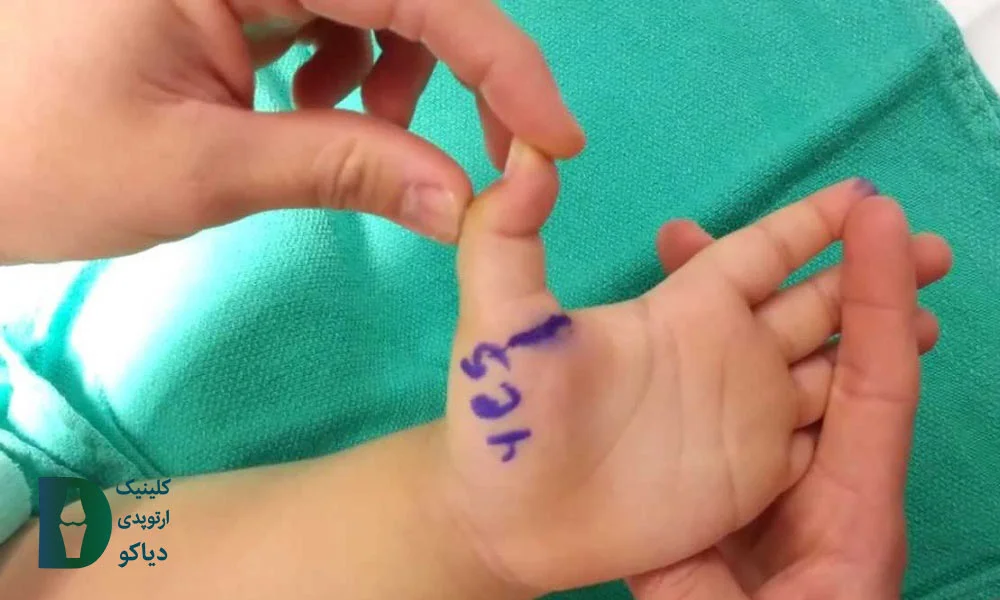

در مقابل، فرم شایع در کودکان عمدتاً مادرزادی است، بیشتر در انگشت شست دیده میشود و اگر تا دو سالگی بهبود نیابد، جراحی ساده بهترین گزینه درمانی خواهد بود. بنابراین برای انتخاب درمان مناسب، باید به سن، محل درگیری، و شدت علائم توجه شود.

انگشت ماشهای در کودکان (بهویژه در شست) معمولاً بهصورت مادرزادی بروز میکند و برخلاف فرم اکتسابی در بزرگسالان، دردناک نیست، اما میتواند باعث گیرکردن دائمی انگشت در حالت خمیده شود. در این حالت، کودک قادر به صافکردن شست خود نیست، حتی با کمک دست دیگر و علت اصلی این مشکل، تشکیل یک گره کوچک (ندول) در تاندون خمکننده و تنگی غلاف اطراف آن است که مانع از حرکت روان تاندون میشود.

نتایج مطالعات روی بیش از ۴۰۰ کودک نشان داده است که درمان جراحی پس از دو سالگی، اثربخشتر و ایمنتر است و در هیچ موردی منجر به عود یا عارضه نشده، در حالیکه درمانهای غیرجراحی، بهویژه در کودکان بالای ۲ سال، در بیش از ۷۰٪ موارد موفق نبودهاند.

درمان غیرجراحی انگشت ماشهای در کودکان زیر ۲ سال تنها در ۳۰٪ و در کودکان بالای ۲ سال فقط در ۲۰٪ موارد موفق بوده، در حالی که جراحی در هر دو گروه سنی نزدیک به ۱۰۰٪ موفقیت بدون عوارض یا عود داشته است (منبع).

آیا جراحی برای کودک ضروریست؟

در برخی کودکان، بهویژه آنهایی که بالای ۲ سال هستند و انگشتشان در وضعیت خمشده قفل شده باقی میماند (گرید 3b یا 4)، درمانهای محافظهکارانه مانند آتل یا تمرینات کششی معمولاً پاسخ نمیدهند. در این شرایط، جراحی نهتنها گزینهای مؤثر، بلکه بهترین راه برای پیشگیری از ماندگار شدن ناهنجاری انگشت در بزرگسالی است.

طبق نتایج مطالعهای، موفقیت جراحی در کودکان ۱۰۰٪ بوده و هیچگونه عارضه یا عود گزارش نشده است. این عمل کوتاه، سرپایی و معمولاً با بیحسی موضعی انجام میشود و روند بهبودی نیز سریع و بدون مشکل است. اگر فرزندتان در این شرایط قرار دارد، توصیه میکنیم بدون نگرانی و با آرامش، مسیر جراحی را با پزشک بررسی کنید تا از بروز مشکلات بلندمدت در رشد دست کودک پیشگیری شود.